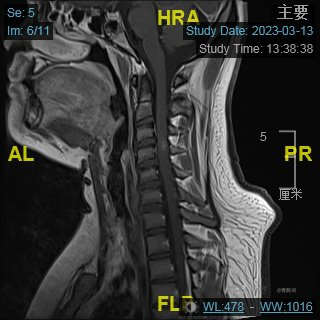

颈部磁共振平扫:

颈部磁共振平扫后增强: